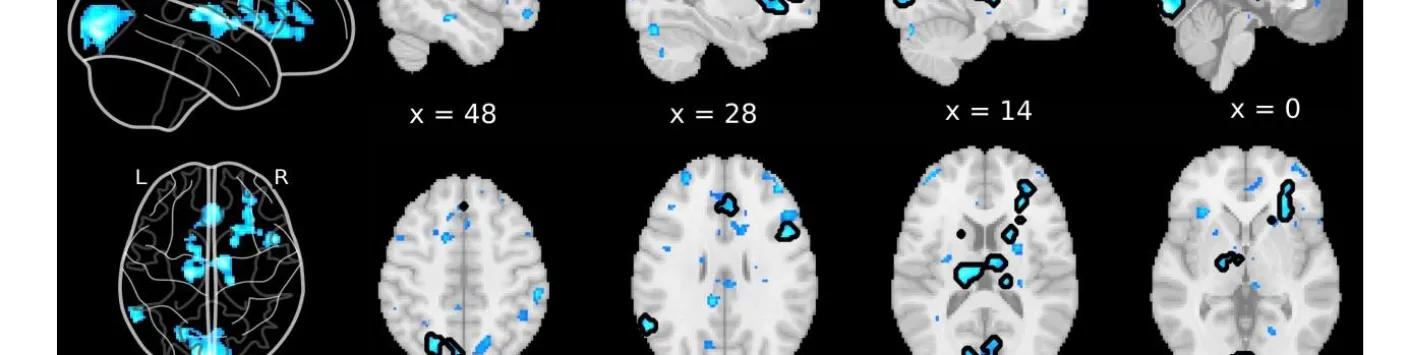

Les désactivations du cerveau entier précèdent les rapports de suppression de l'esprit non induits

➡ Il a été démontré que de telles instructions induisent des activations IRMf dans les régions frontales du cerveau, typiquement associées à la métacognition et aux processus d'auto-évaluation, ce qui suggère que la MB pourrait être le résultat d'une suppression intentionnelle du contenu mental.

➡ Ici, les auteurs de cette étude, dont notamment Paradeisios Alexandros Boulakis, Aspirant FNRS Université de Liège, Sepehr Mortaheb Aspirant FNRS Université de Liège, Steve Majerus, Promoteur PDR FNRS Université de Liège et Athena Demertzi, Chercheuse qualifiée FNRS Université de Liège visent à examiner cette hypothèse en déterminant les corrélats neuronaux de la MB sans induction.